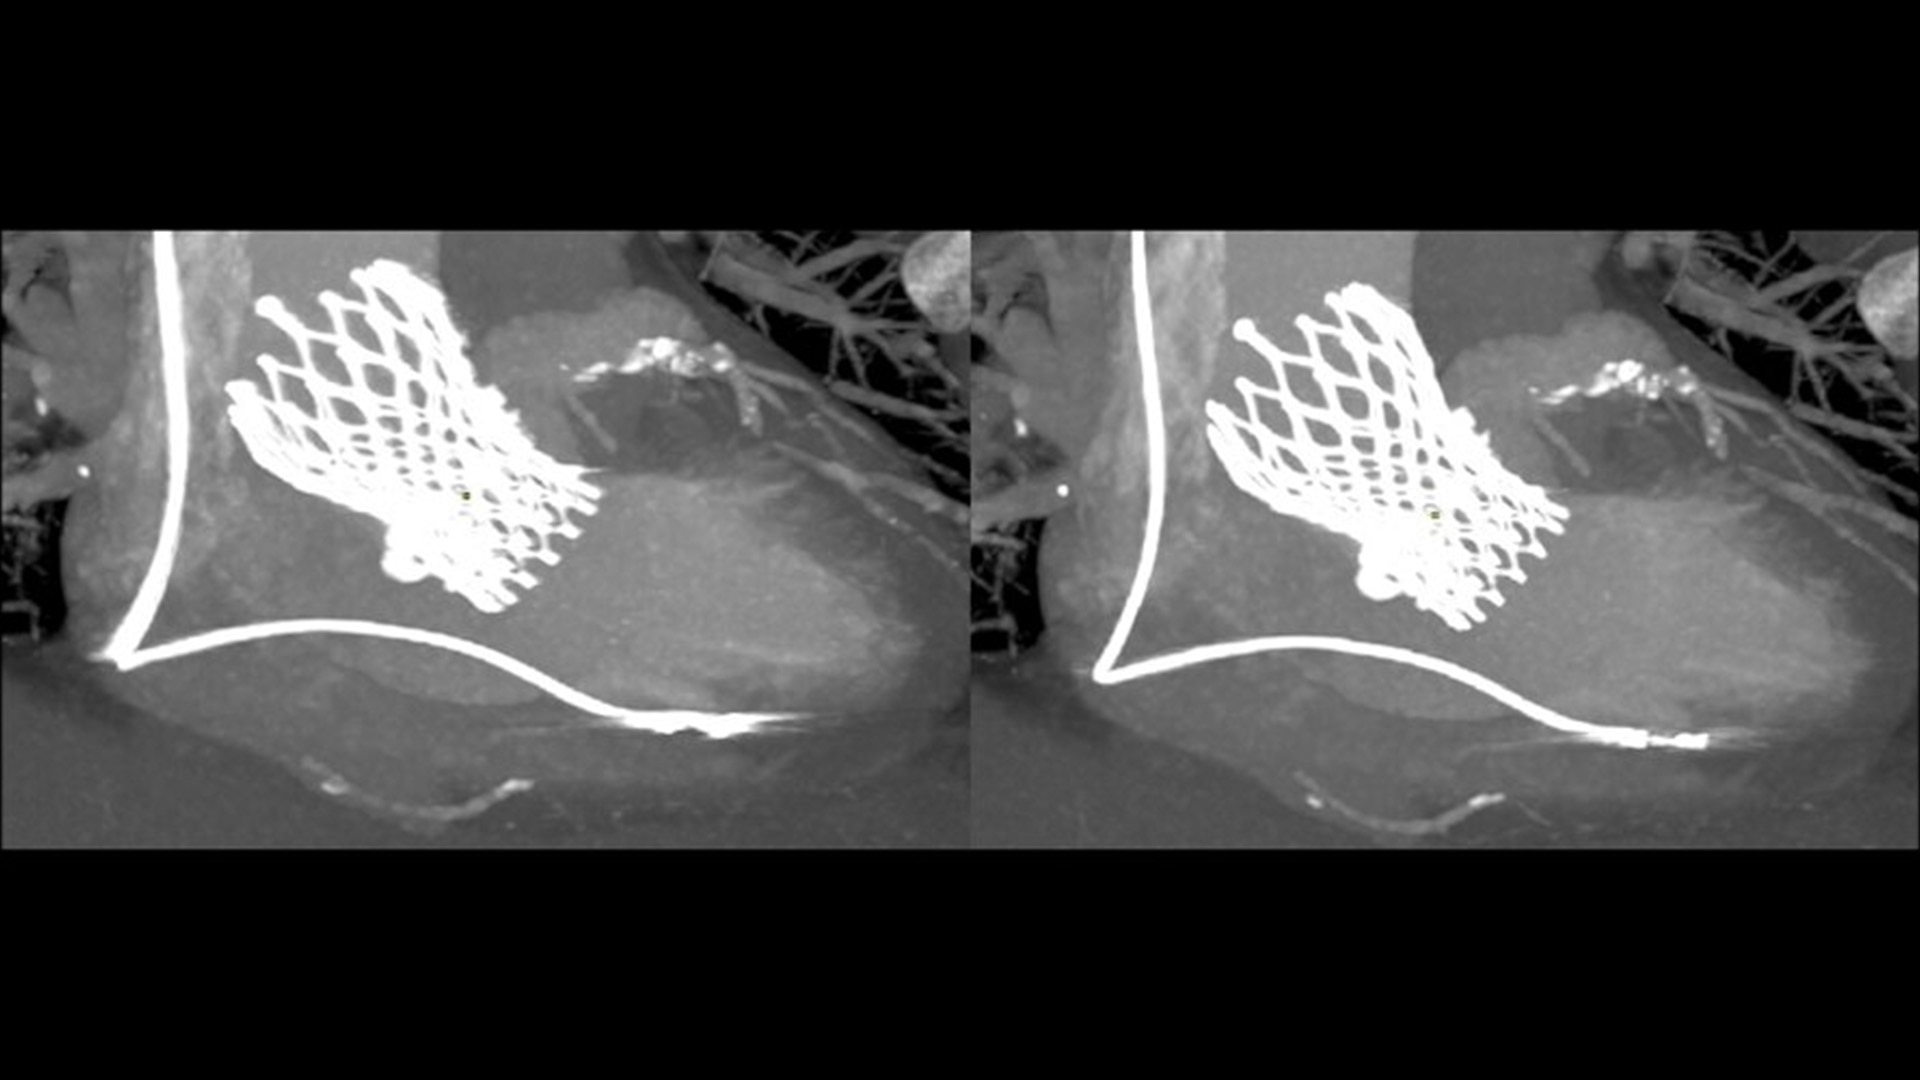

SnapShot Freeze 2

Intelligent and automated whole-heart motion correction for enhanced Cardiac CT imaging.

Motion correction

6x reduction in motion artifacts1

Temporal resolution

19.5 msec effective temporal resolution at 0.23s/rotation gantry speed2